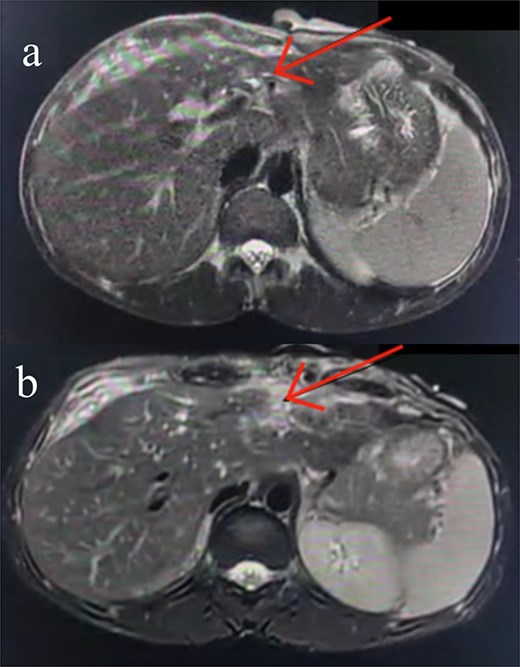

Following stabilization, an abdominal ultrasound showed minimal free intraperitoneal fluid, and a contrast-enhanced computed tomography (CT) scan revealed lacerations in liver segments III and IV with a fluid pocket extending to the abdominal wall, suggestive of bile leakage. A sinus tract connecting the liver to the skin was also seen, along with mild intrahepatic biliary dilation (Fig. 1).

Axial contrast-enhanced abdominal CT images. (a) Subtle injury to the intrahepatic biliary radicals in the left hepatic lobe. (b) Linear laceration on the anterior surface of the liver.